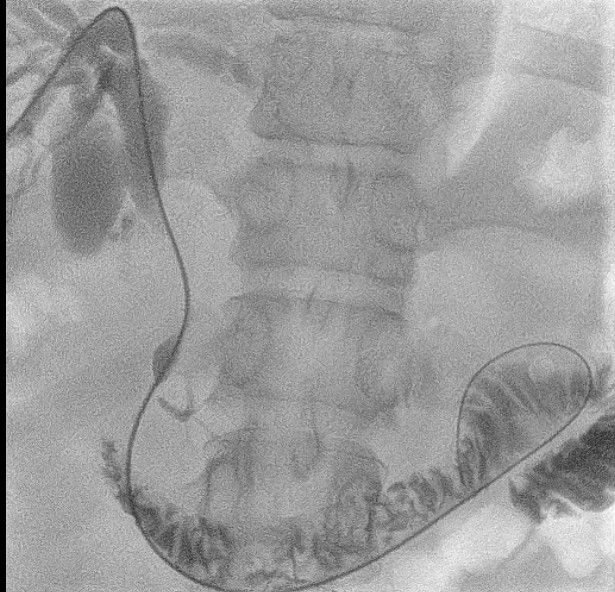

A 45-year-old male patient, with known history gastric carcinoma and previous treatments including gastrectomy with gastrojejunostomy, and partially discontinued chemotherapy, recently faced obstructive jaundice due to lymph nodal metastases. Following an MRCP, a minimally invasive PTBD and SEM biliary stenting were performed under IV anesthesia:

– Cholangiogram identified a tight stricture in the hepatic duct, CBD, and duodenum.

– Post-stenting cholangiogram displayed smooth contrast flow into the duodenum.